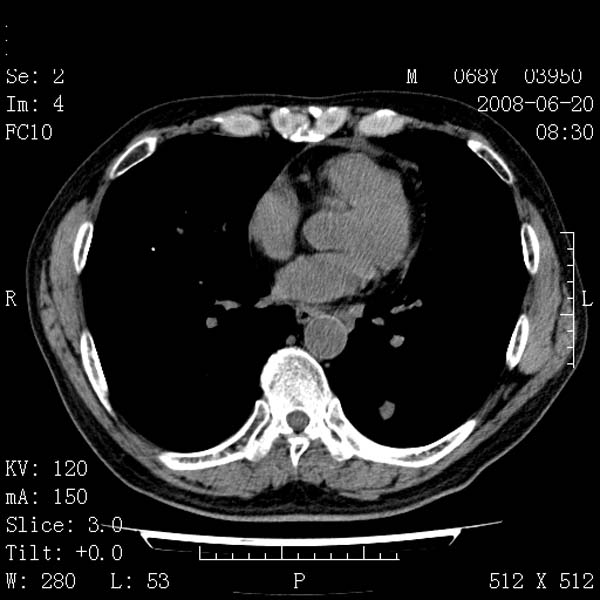

以下是引用守望可可西里在2008-6-24 1:11:00的发言:[br][br] 考虑为周围型肺癌:[br] 1.分叶结节,形态极不规则,蟹足样伸展的恶性浸润特征比较明确。[br] 2.磨玻璃影中由多个更高密度小结节聚集呈梅花瓣样。[br] 3.局部胸膜凹陷征比较明确。[br][br] 另:纵隔胸膜明显增厚、粘连。

以下是引用zjzjr在2008-6-24 11:19:00的发言:[br]支持左下肺周围型肺癌伴右肺转移,纵隔淋巴结转移,心包积液.

以下是引用zhangling在2008-6-24 14:56:00的发言:[br]我们科室意见报告为[br][br]1考虑左下肺周围型肺癌[br]2右肺小结节考虑转移瘤,纵隔淋巴结转移[br]3心包积液. [br] 各位老师分析的相当好 谢意[br]